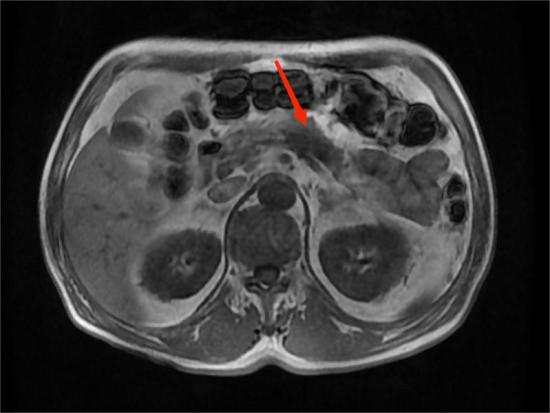

图4A

图4B

图4C

图4D

典型病例4:

男性,59岁,间断左中上腹部疼痛2个月,为隐痛,程度较轻,伴夜间痛。图A:T1WI示胰腺体部见团片状稍低信号影,边界不清。图B:增强扫描示病灶呈弱强化。图C:胰腺体尾部实质萎缩。图D:MRCP示远端胰管扩张。